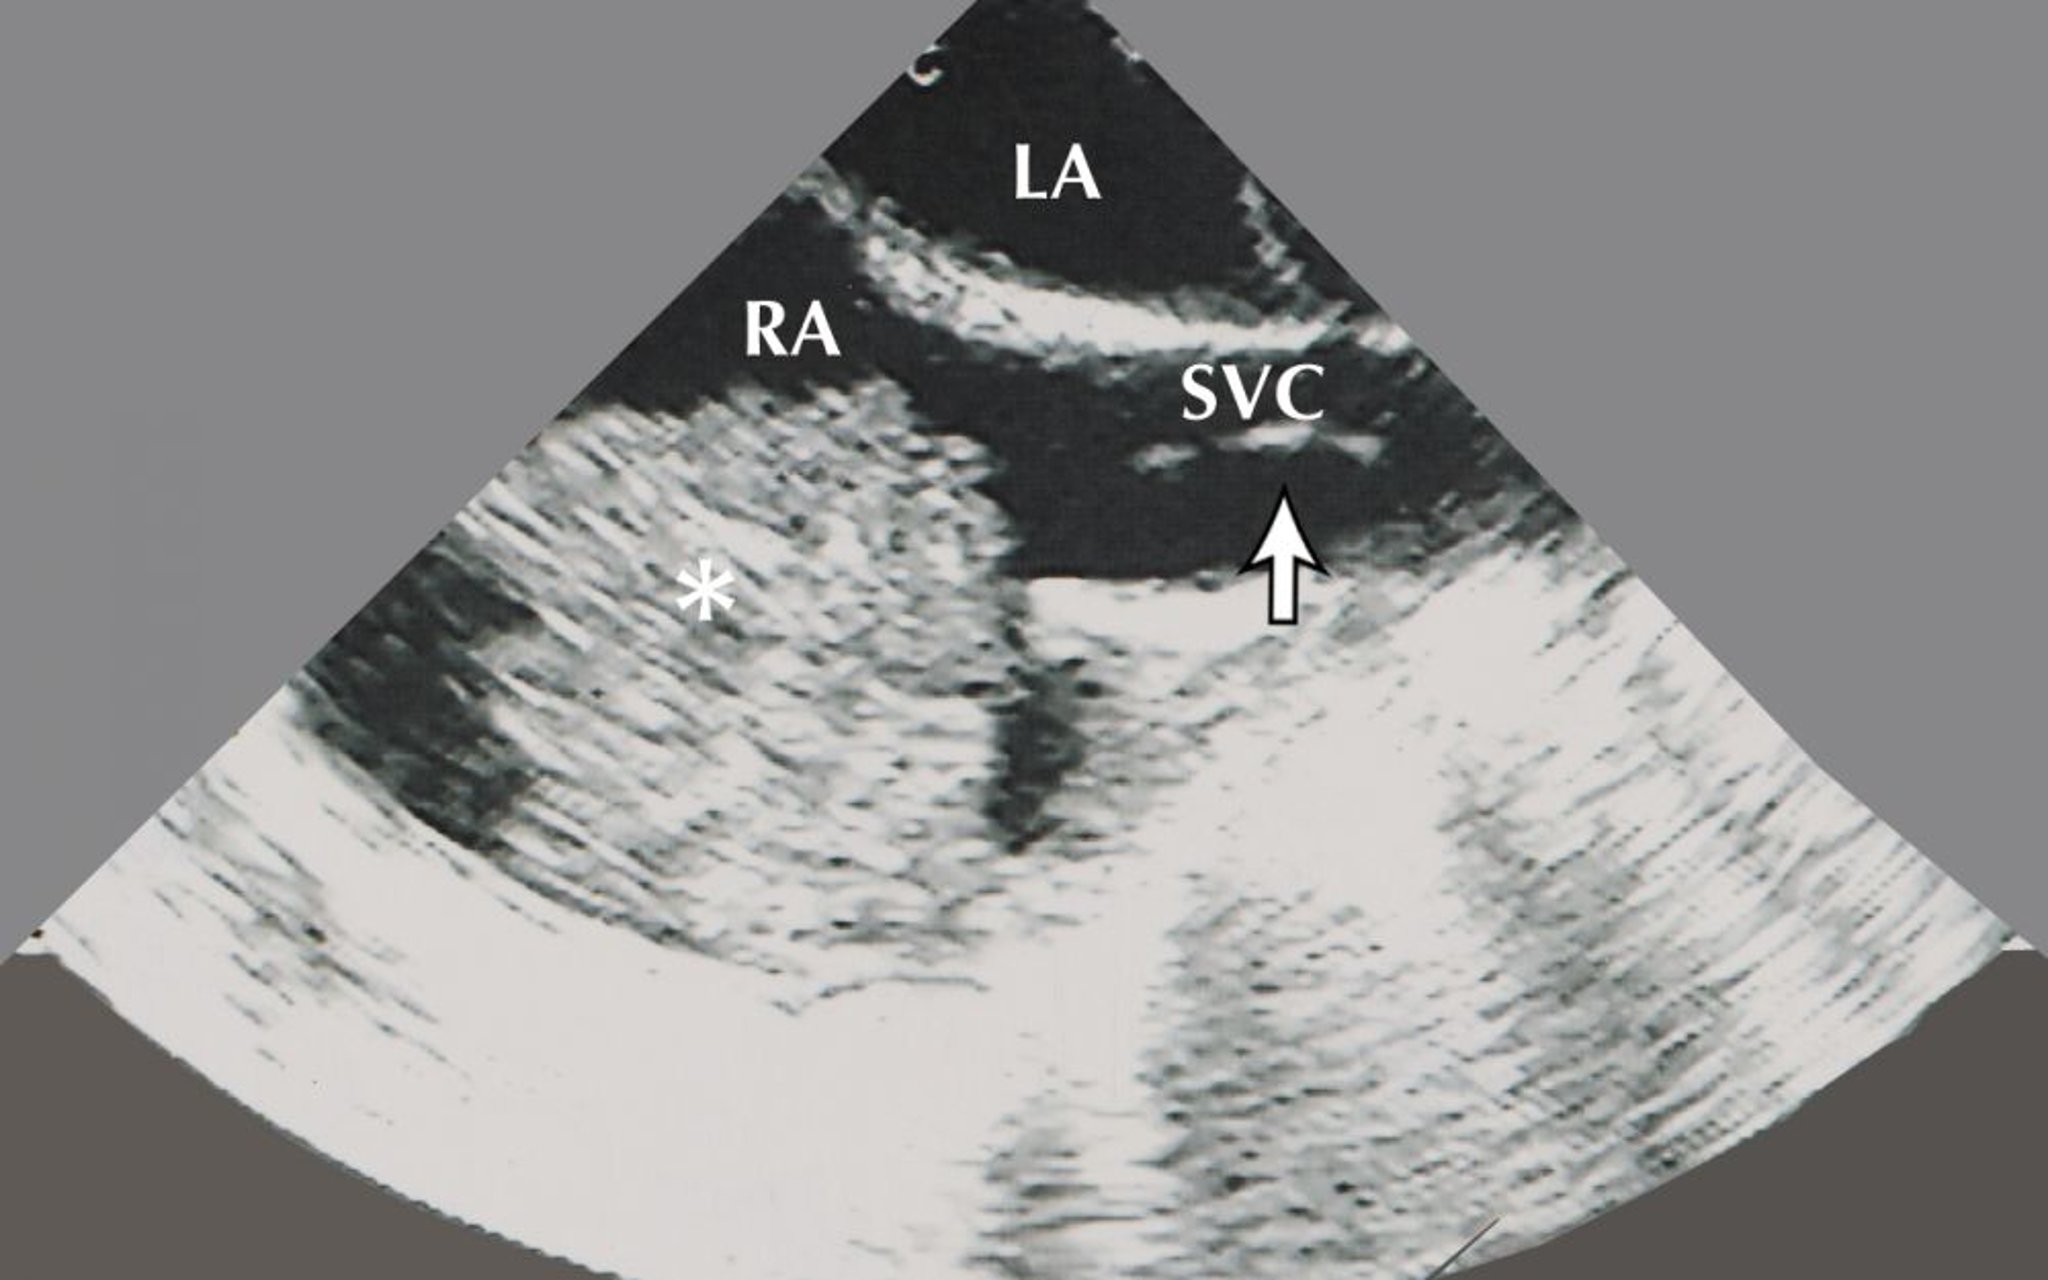

Mixoma auricular (ecocardiografía)

Esta imagen muestra un mixoma auricular (indicado por el asterisco) en la aurícula derecha (AD). También es visible en esta imagen ecocardiográfica la aurícula izquierda y una biopsia por bióptomo (indicada por la flecha) en la vena cava superior.